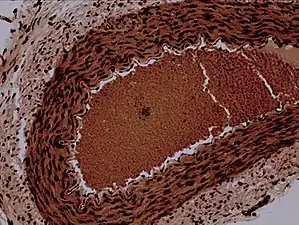

![]() Rabbit arteriole at 100X | |

Arterioles have muscular walls (usually only one to two layers of smooth muscle cells) and are the primary site of vascular resistance. The greatest change in blood pressure and velocity of blood flow occurs at the transition of arterioles to capillaries. This function is extremely important because it prevents the thin, one-layer capillaries from exploding upon pressure. The arterioles achieve this decrease in pressure, as they are the site with the highest resistance (a large contributor to total peripheral resistance) which translates to a large decrease in the pressure.[2]